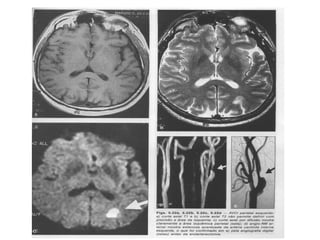

• Icto completo (IC) – DEVH:

– Hemorragia intraparenquimatosa (HIP)

• Locais mais comuns:

–   Gânglios da base

–   Região subcortical dos lobos (+ no lobo temporal)

–   Cerebelo (+ nos lobos cerebelares q no verme)

–   Tronco encefálico (+ na ponte)

Classificação quanto ao modo de instalação dos

sintomas

ÍCTUS = diminuição das funções do cérebro após uma alteração da

circulação do sangue no mesmo

• Icto completo (IC) – AVEH:

– Hemorragia subaracnóidea (HM)

• Comum na artéria comunicante posterior – causa tb paralisia completa do

III n. craniano (oculomotor);

• Pode causar tambem paralisia do pares IV (troclear) e VI (abducente).

• HSA - HEMORRAGIA SUBARACNÓIDEA